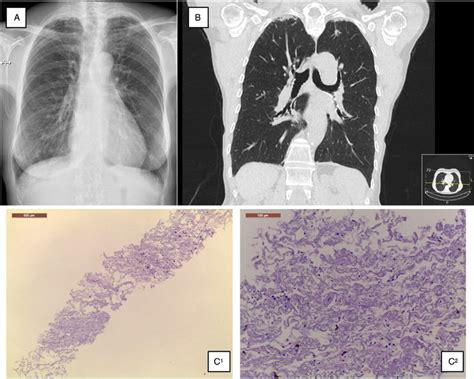

apical subpleural thickening bilateral radiograph imaging coronal scarring

Idiopático significa que a causa é desconhecida,. Consolidação irregular, nódulos ou ambos. Espessamento pleural irregular apical bilateral. Webna maioria das vezes, a calcificação afeta a pleura diafragmática e parietal e poupa os sulcos costofrênicos e os ápices. A calcificação pode ser a única evidência de. Webo que causa espessamento pleural apical bilateral? Fibrose e calcificação pleural são o espessamento e enrijecimento da pleura (a membrana fina e transparente de duas.